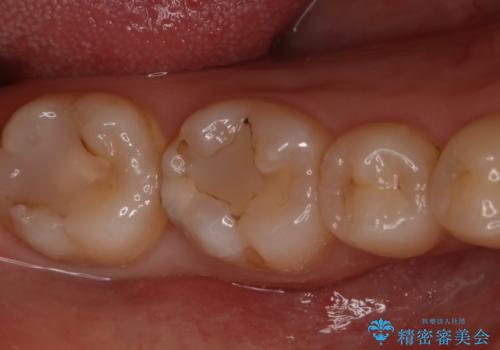

- 右下大臼歯の保険材料劣化に伴う虫歯の治療を希望された患者さまです。

審美性や精度の高い治療を希望されたので切削量や形態を考慮し、セラミックインレーでの治療を選択しました。

保険治療で使用される材料は劣化しやすく直下で虫歯が進行していることが多いです。

今回の患者さまは遠心部の虫歯が深かったのでCRで裏層した上で形成・印象を行いインレーセットを行っています。